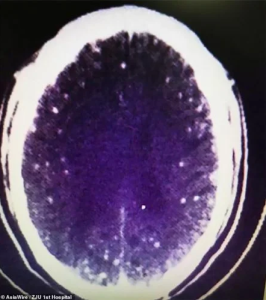

Doctors Pulled 700 Worms Out

Pork and ham are popular dishes for the holidays. But if they are not cooked properly, you could end up with hundreds of worms calling your digestive tract home. A Chinese man named Zhu Zhongfa ate undercooked pork and unknowingly ingested the eggs of the dangerous parasite Taenia solium. As a result, his life was […]